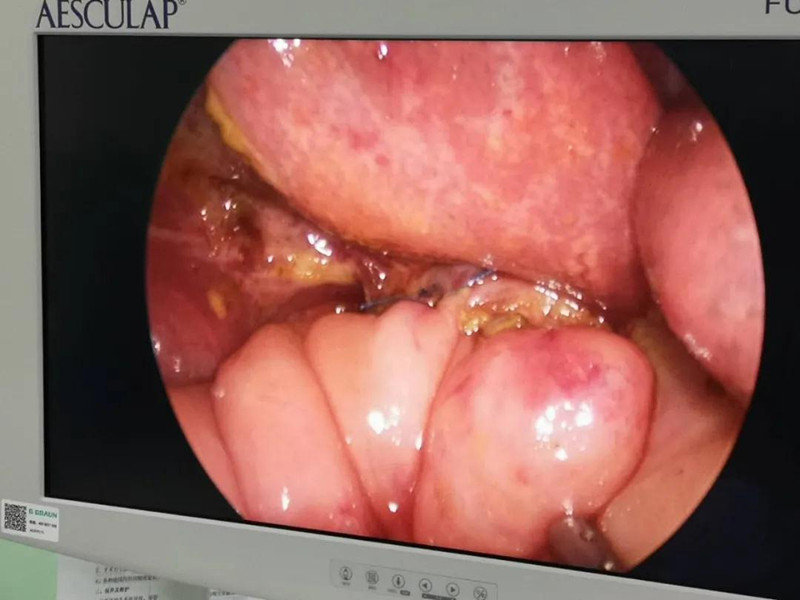

最近半个月,长春市26个月女宝馨馨(化名)脸色不好,全身发黄严重,还伴随发烧。9月23日,馨馨被家人带到a片网站 诊治。经检查,馨馨全身发黄是因为患有黄疸,而黄疸的出现是因为胆总管发生病变,“胆总管呈现囊性扩张,下边出口被堵住,胆汁进不到肠腔里,导致孩子出现黄疸、肝功不好、白土便症状。而且胆总管胀大后,还有癌变的风险,”普外、新生儿外科主任崔钊说,馨馨需要尽快手术。为了减少损伤,崔钊主任团队制定的方案是单孔腹腔镜下胆总管囊肿根治手术。

术前准备完毕。 9月25日,馨馨进入手术室。由崔钊主任带队,按照术前设计的方案,经过8个小时的奋战,手术成功了。馨馨肝总管以下病变的胆总管及胆囊全部切除,肝总管断面与肠管吻合接上,让胆汁直接流到肠腔里,帮助消化。如术后不出现胆瘘、肠瘘,没有梗阻,馨馨以后就可以正常生活了。目前馨馨恢复得很好,黄疸渐渐缓解,肝功正常,白细胞也降下来了,排气、排便都没问题,引尿管里也没有异常东西。